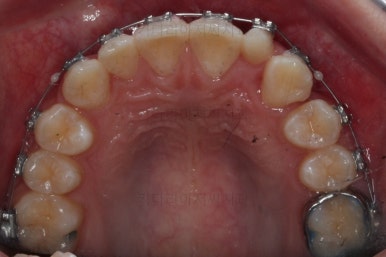

마찬가지로 부산교정치과 키다리아저씨치과에 처음 내원하셨을 당시의 입안 모습입니다.

화살표로 표시된 치아가 작은 앞니 부분인데 크기가 매우 작고 뾰족한 것을 볼 수 있어요. 유치가 아니고 평생 써야 하는 영구치입니다. 이러한 상태를 "왜소치"라고 표현하는데, 치아 크기의 문제로 여러 가지 문제점이 생길 수 있어요.

윗니 치아 사이에 틈이 생길 수 있습니다.(치아 크기가 모자란 만큼 틈이 있는 것이죠.)

아래 앞니가 삐뚤어질 수 있습니다.(비율상 아랫니가 상대적으로 커지기 때문에 삐뚤어지게 됩니다.)

미적으로 좋지 못합니다.

또 다른 문제는 위아래 앞니가 매우 많이 겹쳐져 있어서 아래 앞니가 거의 보이지 않는다는 점입니다.

그 다음 문제는 왼쪽 송곳니 부분(붉은색 동그라미)이 유치가 남아있고, 영구치가 매복되어 있는 경우였어요.

처음 장치를 부착한 이 후 8개월이 흐른 시점이네요. 꽤나 오랫동안 천천히 송곳니를 가지런하게 해줘요.

치료 10개월째의 모습입니다.

이정도면 다 끝난 것 같은 느낌이 드시지 않나요? 과개교합도 개선시켰고 매복치아 덧니도 가지런하게 했어요.